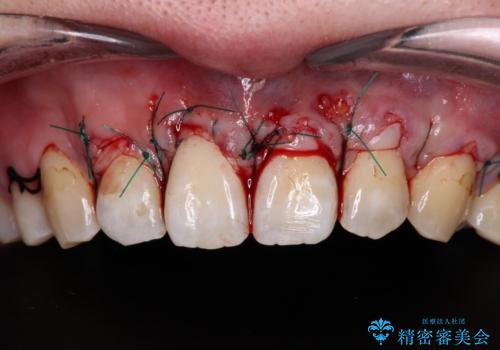

歯肉退縮に対して、上顎からの結合組織移植術(CTG)により、歯根の被覆を行うとともに、歯肉の厚みを増すことで将来の退縮リスクを抑制することとしました。

必要な被覆量が多かったため、満足のいく被覆を達成するには2度の手術が必要と思われましたが、生着がよく、術後の注意事項を徹底したことで、十分な被覆量を達成することができました。